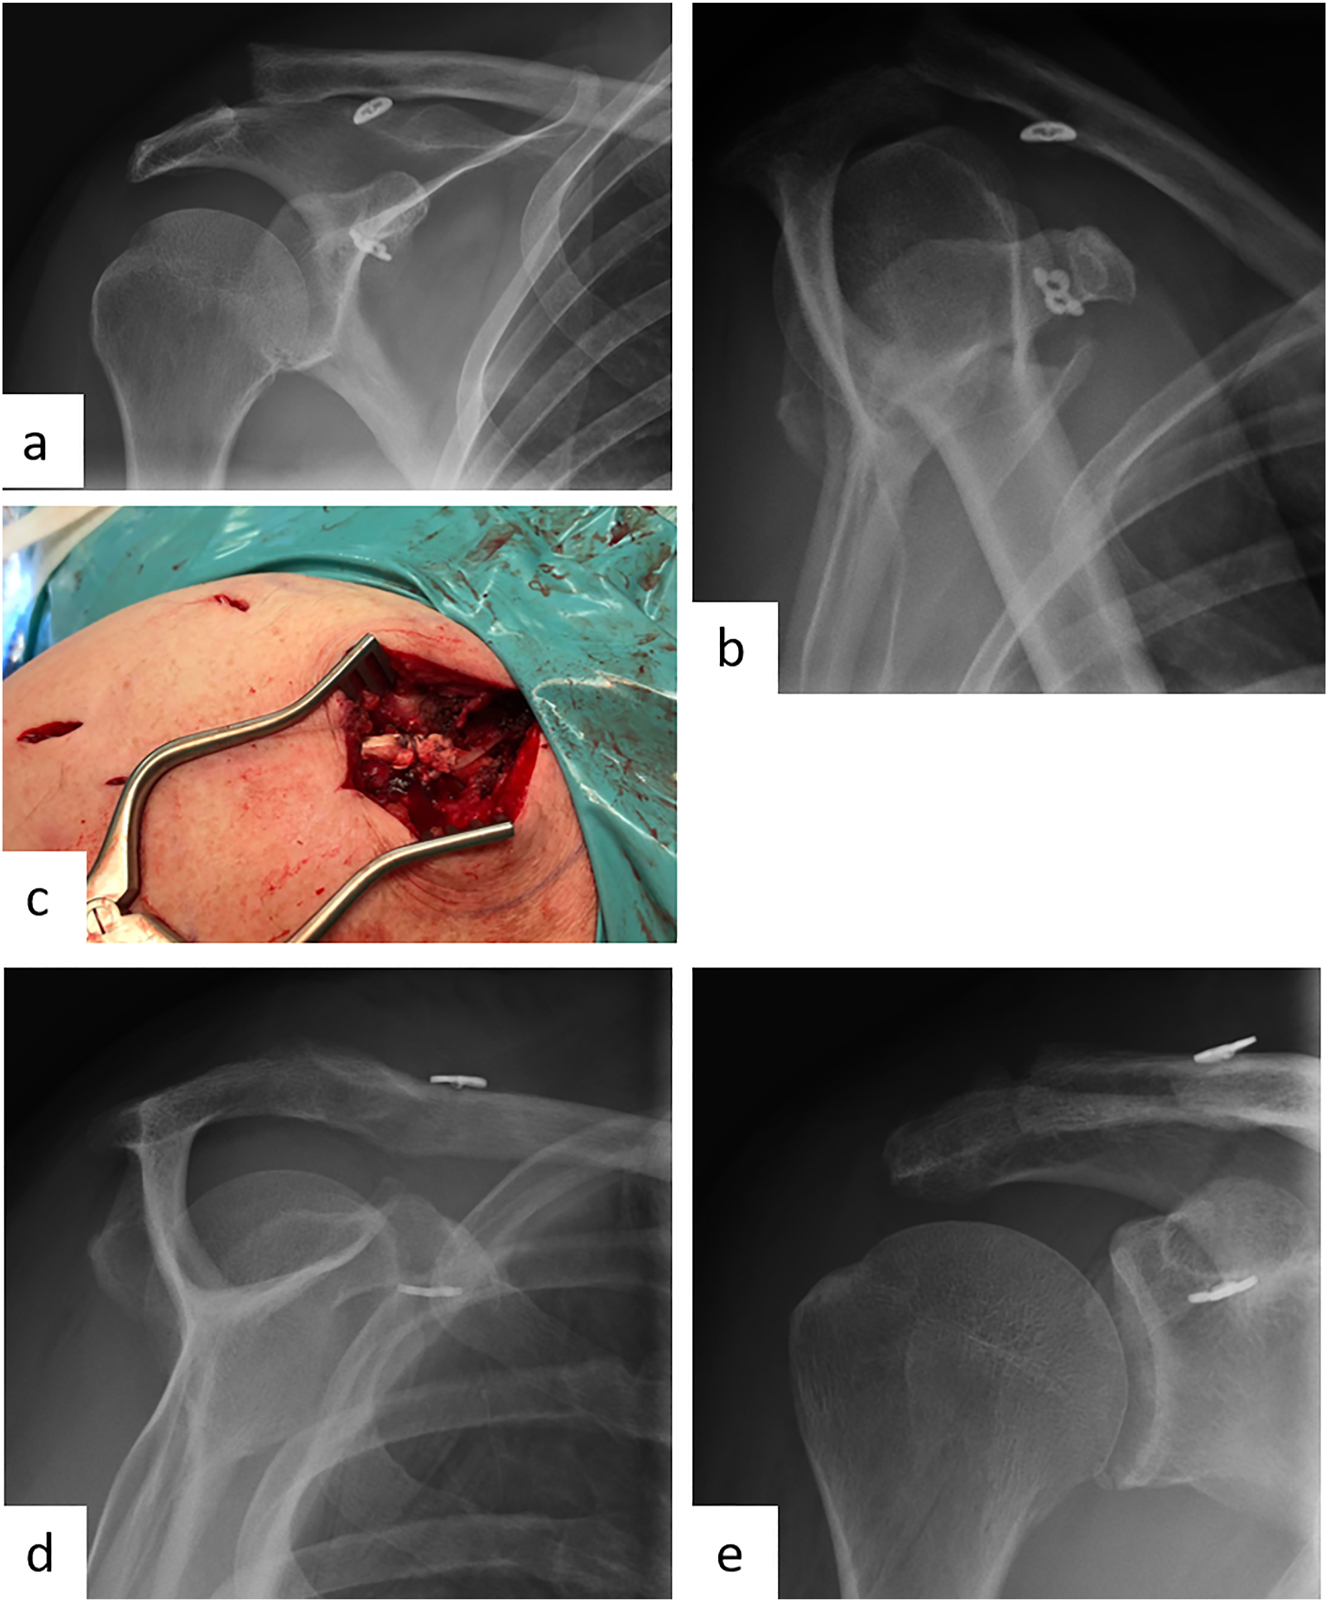

The standard radiographic approach to suspected AC joint injury includes an axial radiograph of the affected shoulder. Here, posterior instability can be visualized. In addition, bilateral Alexander radiographs are performed to evaluate horizontal instability and Zanca stress radiographs with 10 kg weights are performed to show vertical instability in a lateral comparison (Figure 4) [45, 46, 49]. A panoramic image with imaging of the upper thoracic aperture looking at both AC joints should be avoided due to the high radiation exposure with the thyroid gland being particularly at risk. Furthermore, from a certain patient age, preoperative MRI diagnostics of the shoulder can be considered due to the increased incidence of glenohumeral concomitant pathologies [43]. However, this is not yet part of the diagnostic gold standard. CT diagnostics are reserved for special cases, such as a coracoid fracture.

Female patient (50 y), left shoulder, acute acromioclavicular joint dislocation (Rockwood 5) (preoperative X-ray): a – Zanca stress radiographs with 10 kg weights left shoulder, b – Zanca stress radiographs with 10 kg weights right shoulder, c – Alexander radiograph left shoulder, d – Alexander radiograph right shoulder, arthroscopically supported vertical and horizontal stabilization with a TightRope, postoperative X-ray: e – Zanca, f – Outlet view.

The senior authors institution suggests that acute AC joint dislocations are treated arthroscopically using the Endobutton technique (Figure 4). Anesthesia is performed under general anesthesia. The patient is positioned in beach chair position with head rest, and a pneumatic arm holder is mounted for controlled movement of the arm. A sterile integrated image transducer for visualization of the burr channels is positioned. The three standard portals (posterior, anteroinferior, anterolateral) are set for arthroscopic access. First, a diagnostic reflection of the shoulder joint is performed via the posterior portal. Possible concomitant pathologies can be detected here and, if necessary, directly corrected. After the diagnostic arthroscopy, a lateral transtendinous arthroscopic approach is made, through which optical imaging is now performed. From the lateral view, arthroscopic visualization of the coracoid arch can now be performed. Via the anterioinferior working portal, the subcoracoidal preparation is now performed in the first step. Next, an approximately 2–3 cm longitudinal skin incision is made above the lateral clavicle to prepare it as well. Anatomical reduction is achieved by applying caudoventral pressure to the AC joint with additional cranialization of the arm via the arm holder. A slight overcorrection is recommended in accordance with the study to counteract postoperative loss of correction. Reduction is held by a k-wire. To perform the transclavicular-transcoracoidal drilling for vertical stabilization, the insertion handle is placed below the coracoid base. The drill is performed under visual arthroscopic and image intensifier-assisted radiological control with an entry point between the attachments of the two CC ligaments and an exit point at the base of the coracoid. In the next step, a shuttle suture is now used to place the Endobutton system with double button implant (e.g., DogBone with Tiger and FiberTape, Arthrex, Naples, FL, USA). The buttons come to rest inferior to the coracoid and over the clavicle. The suture of the clavicular button is left undetached. In the next step, minimally invasive horizontal stabilization is performed using suture cerclage. Via a lateral stab incision, transacromial drilling is performed with subsequent overdrilling by a cannulated drill (2.7 mm) under radiological control. Finally, one leg of each tape is passed laterally through the drill channel with the aid of a shuttle wire and then returned. Finally, the tapes are tightly knotted together under lateral pressure on the acromion. The result is seen in vertical and horizontal stabilization (Figure 4). The joint space of the AC joint should be reduced again to a normal value between 1 and 6 mm. Finally, closure of the deltotrapezoidal fascia and suturing of the wound is performed. A sterile wound dressing is applied and the patient is removed from the bed.

Male patient (55 y), right shoulder, chronic acromioclavicular joint instability with loss of reduction after surgical displacement of an acute Rockwood 3B injury 3 months ago (preoperative X-ray): a – Zanca stress radiograph with 10 kg weight, b – Alexander radiograph, c – arthroscopically supported vertical and horizontal stabilization with a TightRope and an additional autologous Hamstring-tendon augmentation, postoperative X-ray: d – Outlet view, e – a.p.